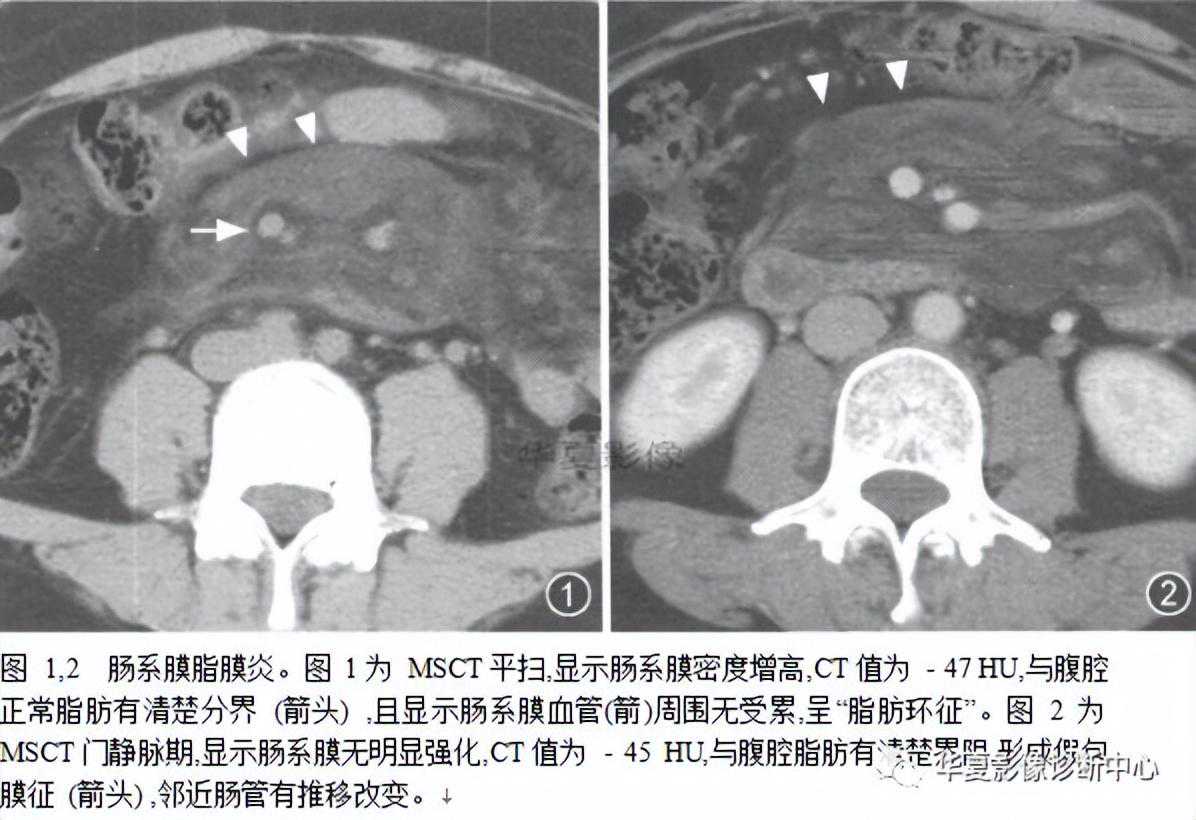

肠系膜脂膜炎的CT表现。肠系膜脂肪组织密度增高(-40--60H。),呈边界清楚、密度不均匀的单个或多个软组织密度肿块,肿块围绕系膜大血管但不累及血管,肠系膜血管周围可有脂肪存在,形成脂肪环征。

肠系膜脂膜炎以慢性毙比细胞浸润,脂肪坏死和纤维组织形成“假肿瘤结节”为特征,包绕但不侵犯肠系膜血管,肠系膜曲静脉血管位于病变内,邻近血管脂肪密度正常,形成脂肪环征。

CT是诊断肠系膜脂膜炎的有效方法。典型CT表现为与腹膜后脂肪密度相比肠系膜脂肪组织密度增高(-40~-60Hu).呈边界清楚、密度不均匀的单个或多个软组织密度肿块,其内可见脂肪密度和低密度囊变区。肿块围绕系膜大血管但不累及血管,肠襻向四周移位。部分表现为肠系膜根部围绕肠系膜血管以脂肪成分为主的肿块,内有散存放射状、条索样、结节样软组织密度区。有时表现为有包膜的密度不均匀肿块,内有脂肪、水样或软组织密度区。少数表现为多房囊性肿块(由于淋巴管和血管阻塞引起的淋巴管扩张)。国内外文献报道缩窄性肠系膜炎有如下特征性表现:①脂肪环征,肠系膜血管周围可有脂肪存在,形成脂肪环征,其出现率为85%~88.8%;②假包膜征,肿块周阿有条带状软组织密度影环绕,病理上为纤维组织,其厚度一般为3mm,小超过iOmm,出现率为50%--66.6%,③软组织结节,为肠系膜淋巴结散在分布于肿块中,多数5mm,80%的患者有此征象;④增强前后无明显密度改变,而其内肿大淋巴结可出现增强,可能与淋巴结的炎性改变有关。